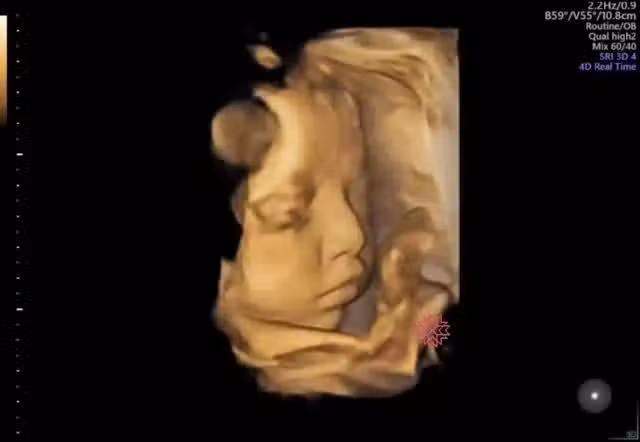

通常懷胎一段時間後,孕媽咪就開始可以感受到寶寶胎動,到了懷孕中後期胎動也會越發明顯,有時候還可能會看到孕肚鼓起來、肚皮在動~也讓人不禁好奇寶寶在子宮裡會做些什麼呢?婦產科蘇怡寧醫師就分享了一段寶寶超音波影片,畫面中寶寶竟有瞬間睜開眼睛,還露出嘟嘴微笑的表情,讓不少網友們紛紛嘖嘖稱奇、被萌了一把~

(圖:翻攝自FB/蘇怡寧醫師愛碎念,以下同)

蘇醫師在臉書粉專發文,表示不少準媽咪在產檢時都會問「寶寶在肚子裡眼睛會不會打開?」因此便PO出一段4D超音波影片,證實寶寶在子宮內確實是會睜眼的,只不過睜眼的時間非常短並不容易察覺到,但蘇醫師也說寶寶睜不睜眼其實不重要,「因為你子宮內沒裝燈,眼睛打開了應該也沒什麼好看的。」